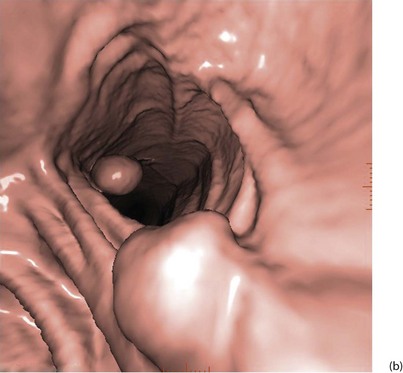

With improved technology, CT is increasingly used for large bowel examination. It can be performed without laxative preparation where it would be acceptable to miss small polyps, for example in suspected obstructing lesions. CT can be useful in the frail elderly when a right-sided colonic cancer is suspected because of anaemia or a palpable mass. For a more complete examination, CT colonography (also known as CT coloscopy or virtual colonoscopy) requires full bowel cleansing. During the procedure, air or carbon dioxide is insufflated into the colon; the technique is sensitive enough to detect lesions larger than 1 cm. The investigation is quicker and less unpleasant than barium enema and has replaced it altogether in some units. Hundreds of images are produced and the best are viewed on workstations along with reconstructed axial and 3D images of the bowel lumen (see Fig. 5.5).